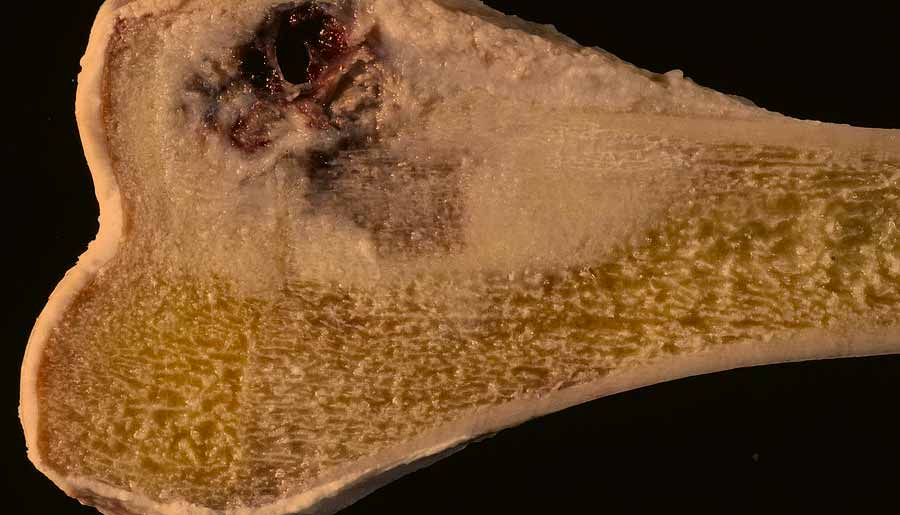

Kako izgleda tumor kostnega raka? Vprašanje anonimne stranke

Tumorji kostnega raka so običajno različnih velikosti, oblik in tekstur ter se lahko pojavljajo v različnih delih kosti.

Tumorji kostnega raka se lahko pojavljajo znotraj kosti ali pa se širijo v okolno mehko tkivo. Nekatere vrste kostnih rakov, kot je osteosarkom, imajo pogosto videz trdnega, gostega tumorja znotraj kosti.

Drugi tipi kostnih rakov, kot so hondrosarkom ali Ewingov sarkom, imajo lahko drugačne značilnosti. Pomembno je poudariti, da laično opazovanje tumorja ni diagnostično zanesljivo. Diagnozo kostnega raka postavi strokovnjak na podlagi celovite klinične ocene, slikovnih preiskav in histološke biopsijske analize.